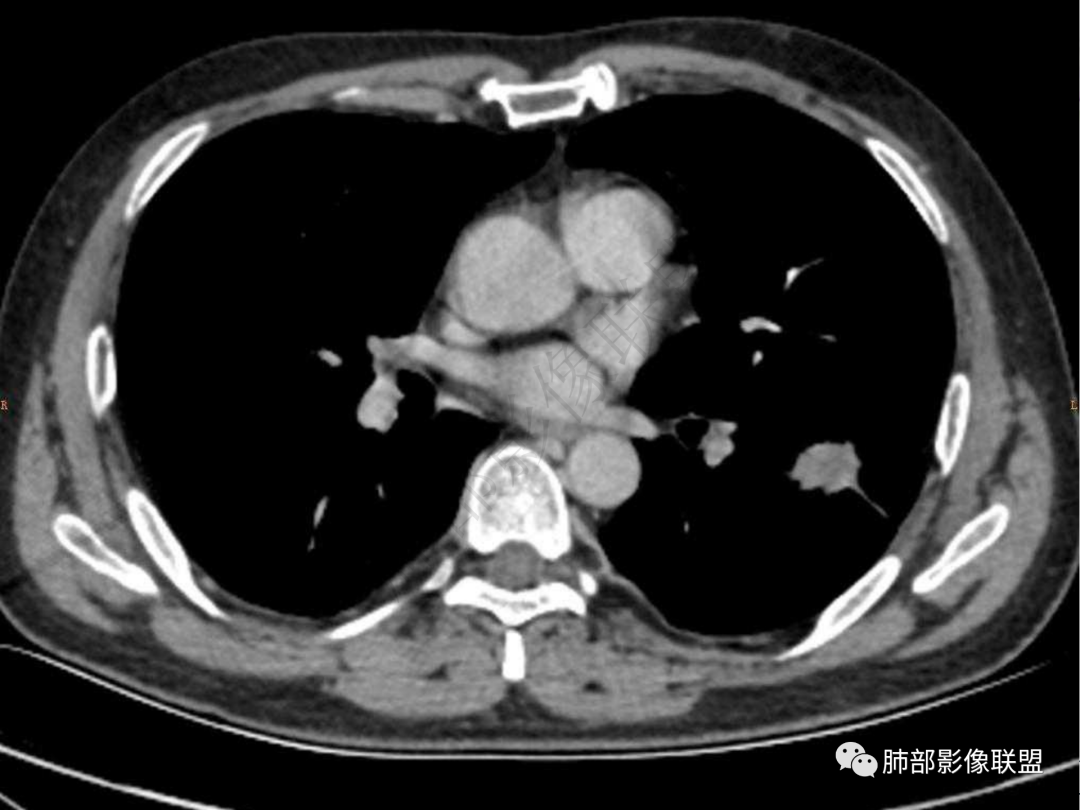

4.实性部分不均匀环形强化并显示一小范围低密度坏死区或空洞。较之肺窗,整体纵隔窗范围较小,提示病灶并不十分密实。抑或为不同时段图像。

六:增强扫描:

肺脓肿:环形强化,强化较显著。如出现明显囊壁样强化甚至边缘“憩室”样突出,高度支持肺脓肿。